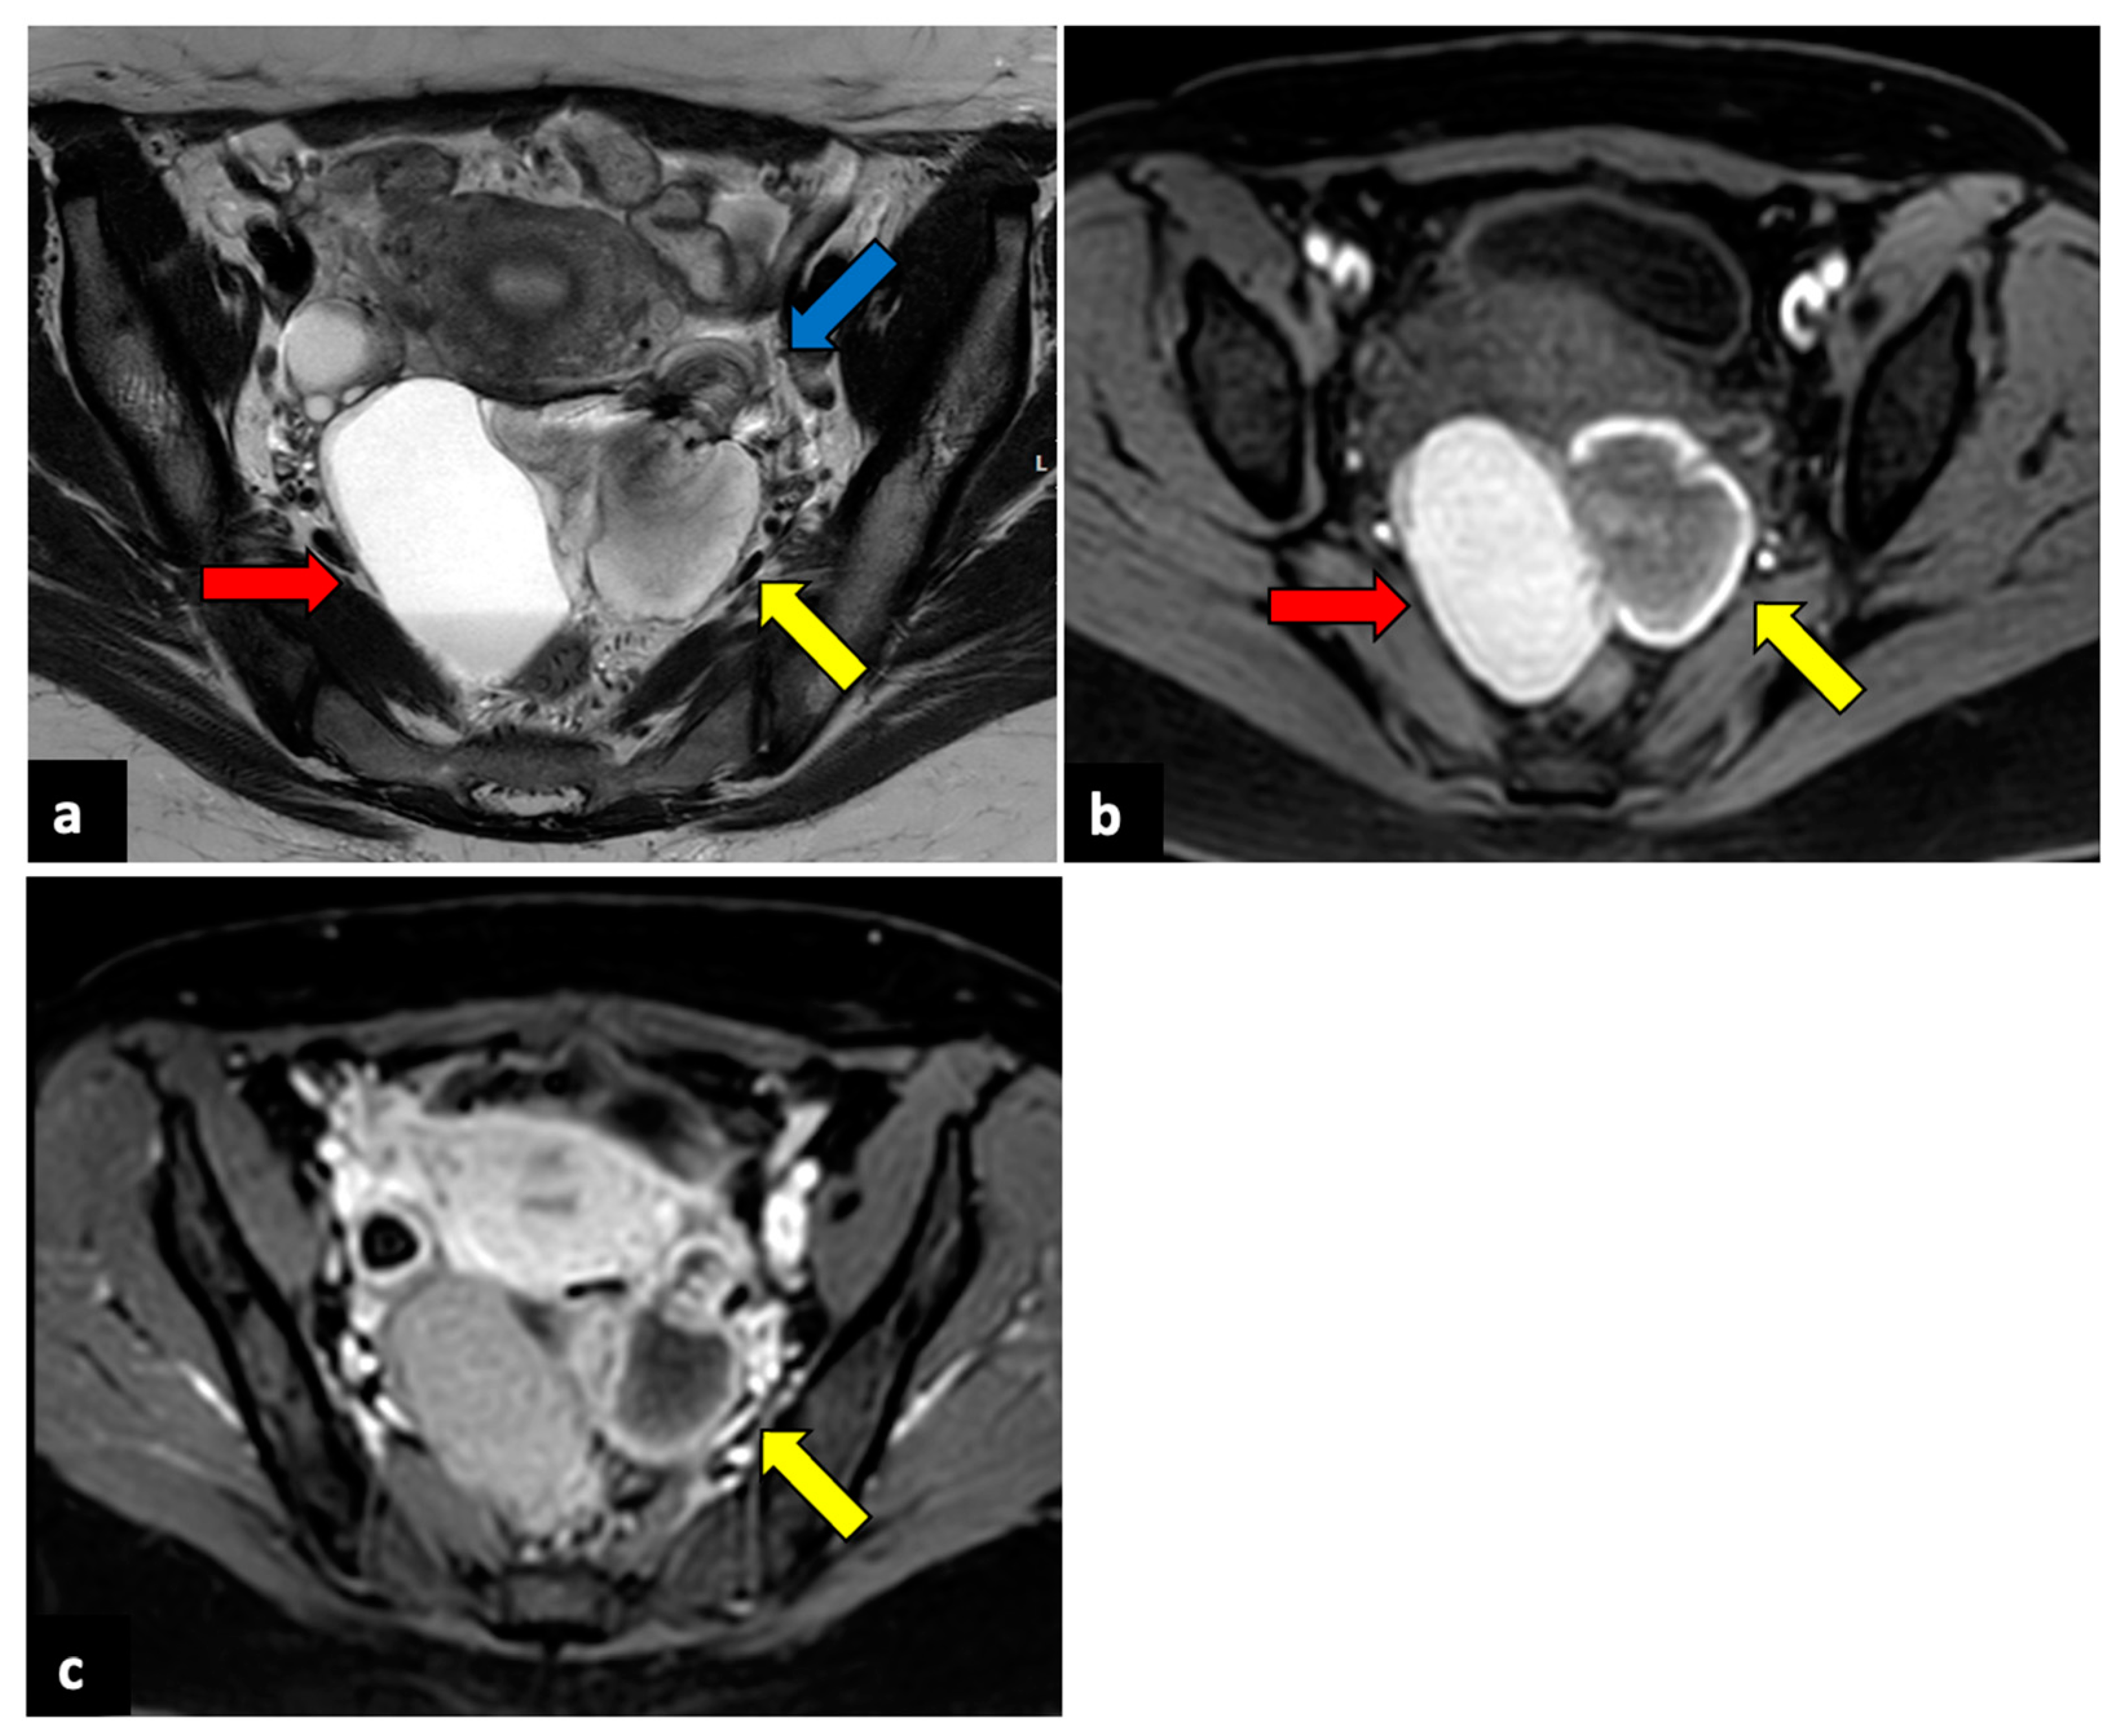

Figure 3.

Left ovarian torsion in a thirty-nine-year-old patient with acute pelvic pain. Axial T2-weighted (a) and T1-weighted fat saturated before (b) and after (c) gadolinium MR pelvic images show an enlarged left ovary located in the Douglas pouch (yellow arrows), with and adjacent twisted vascular pedicle (“whirlpool sign”, blue arrow). The ovary presents a peripheral high signal on T1 extending to the pedicle (rim of methaemoglobin) without enhancement upon post-contrast sequences. A large cystic lesion arises from the left ovary with an internal high signal on both T1 and T2 (red arrows) and declivous sediment of low signal on T2, suggestive of a haemorrhagic cyst. The patient underwent a laparoscopic left adnexectomy, and pathology confirmed the diagnosis of ovarian torsion possibly due to the haemorrhagic cyst.